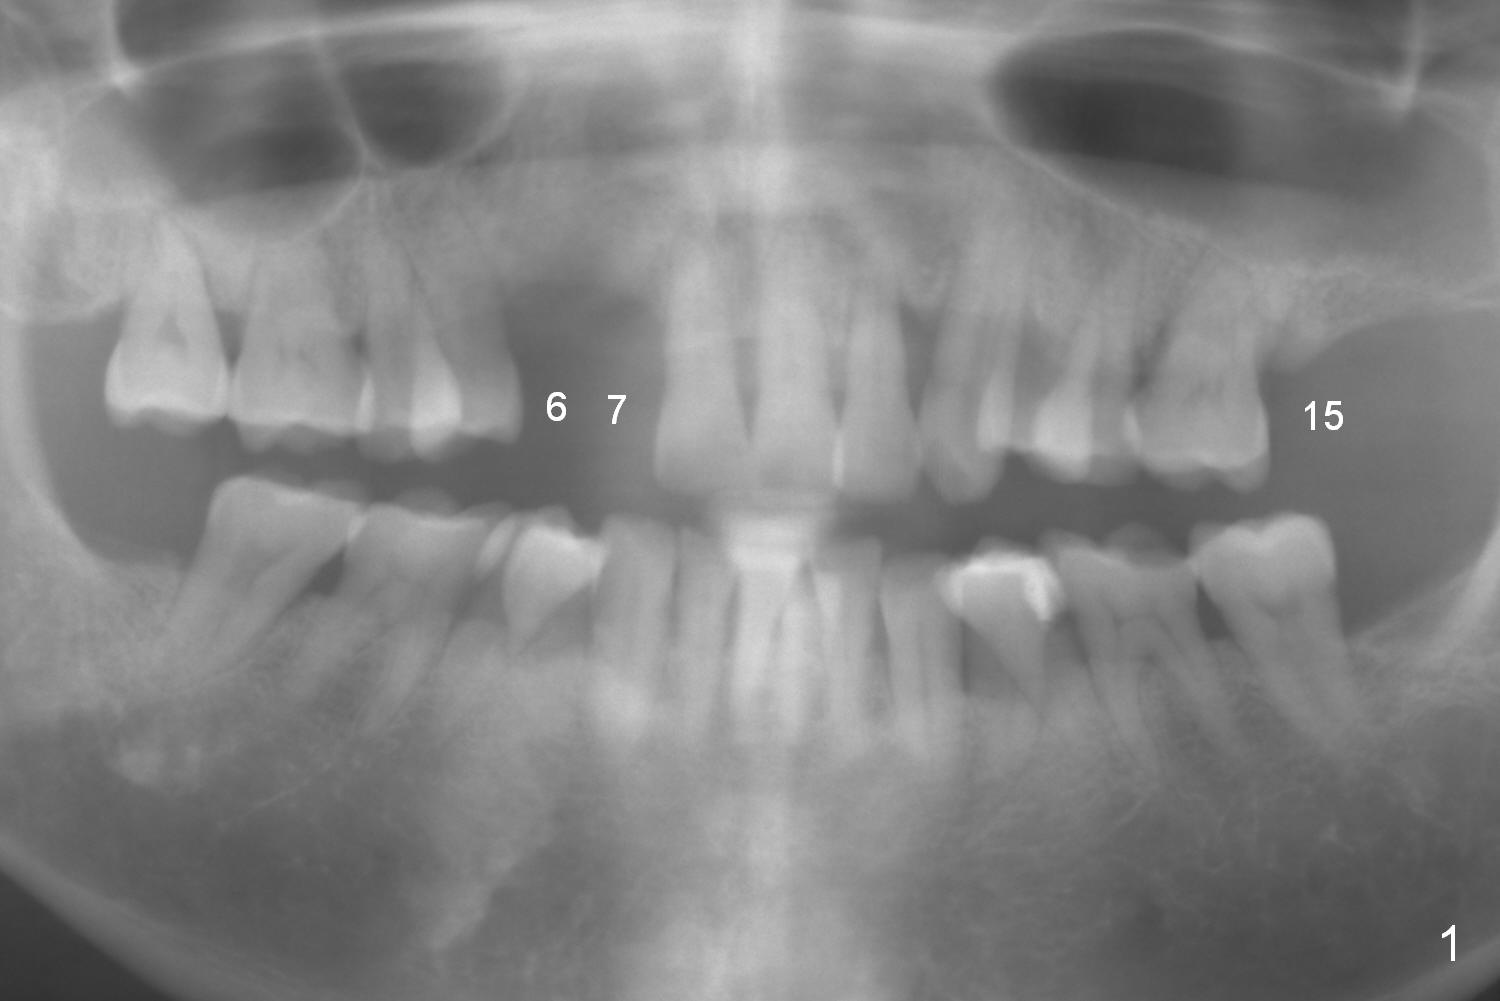

A 54-year-old man has crowded dentition with moderate to advanced periodontitis (Fig.1) and bruxism (exostosis (Fig.6 *)). It is essential to re-establish complete dentition by placing implants at #6, 7 and 15 initially and more when other teeth are lost. The ridge at #6 and 7 is moderately atrophic (Fig.7), while that at #15 severely atrophic (Fig.8). Due to narrow mesiodistal space at #6 and 7 (Fig.2), narrow and 1-piece implants may have to be placed (Fig.3).